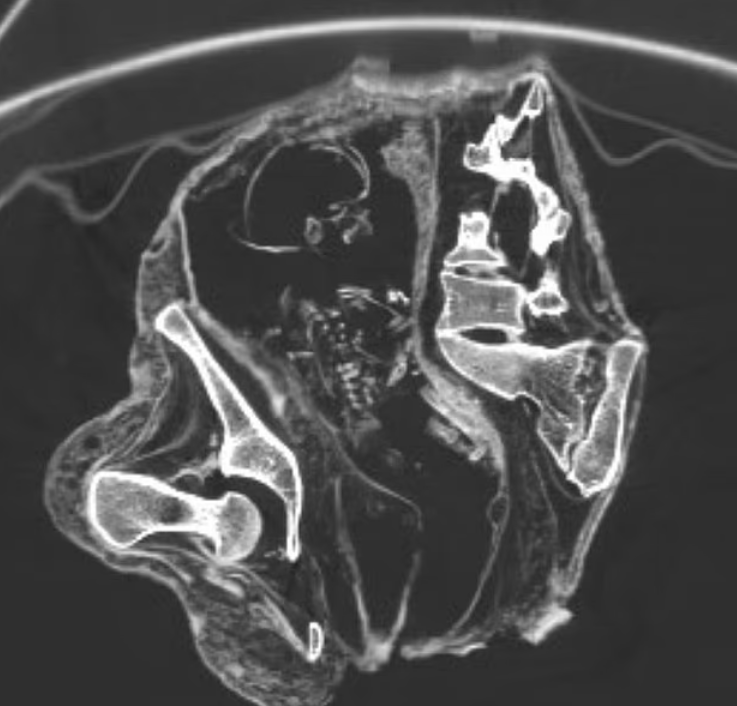

وأظهرت الأشعة المقطعية "الجنين" مستلقيا على ظهره، ورأسه إلى الأسفل بالقرب من منطقة البطن وصدره وذراعيه أقرب إلى منطقة الحوض.

وأشار العلماء إلى أن عظامه كانت لا تزال طرية، وبدأت للتو في التصلب، عندما مات مونتسيرات، تاركًا أجزاء من العمود الفقري والأضلاع غير قادرة على الاندماج معًا.

وقاموا بتحديد عمر "الجنين" بناءً على حجم عظم الفخذ، الذي يبلغ طوله 43 ملم، والذي يستخدم لتقدير عمر الحمل في الموجات فوق الصوتية قبل الولادة، مما يشير إلى أنه كان أقل من 30 أسبوعًا.

وقال إن عمليات المسح تشير إلى أن الجنين قد جف داخل الرحم مع مرور الوقت.

ومع تقلص الأنسجة، احتفظت عضلات الرحم بشكلها العام، ولكن تغيرت عظام الجمجمة والوجه.

وعندما أعاد العلماء بناء الجنين رقميًا، وجدوا أن وجهه قد تحول إلى الخلف.

وفي وقت الوفاة، كانت عظام الجنين لا تزال طرية ولم تتشكل بشكل كامل، مما يجعلها أكثر عرضة للتشوه أثناء التحنيط، بحسب الباحثين.

وقال العلماء إن هذا يفسر سبب ظهور العمود الفقري والأضلاع مكسورة أو غير منتظمة في عمليات الفحص.